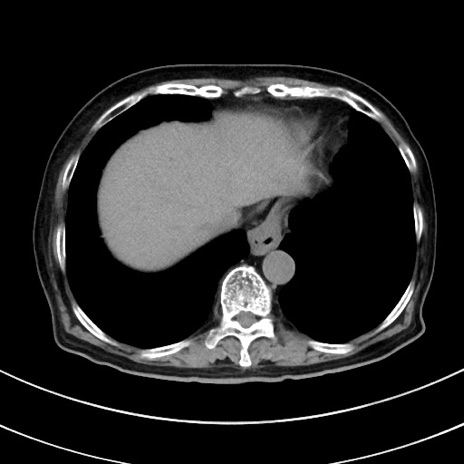

冠状断像

【症例】70歳代 女性

【主訴】心窩部痛

【現病歴】延髄病変の精査・加療にて神経内科入院中。本日より心窩部痛あり。

【身体所見】右下腹部を中心に圧痛と反跳痛あり。

【データ】WBC 10900、CRP 0.02